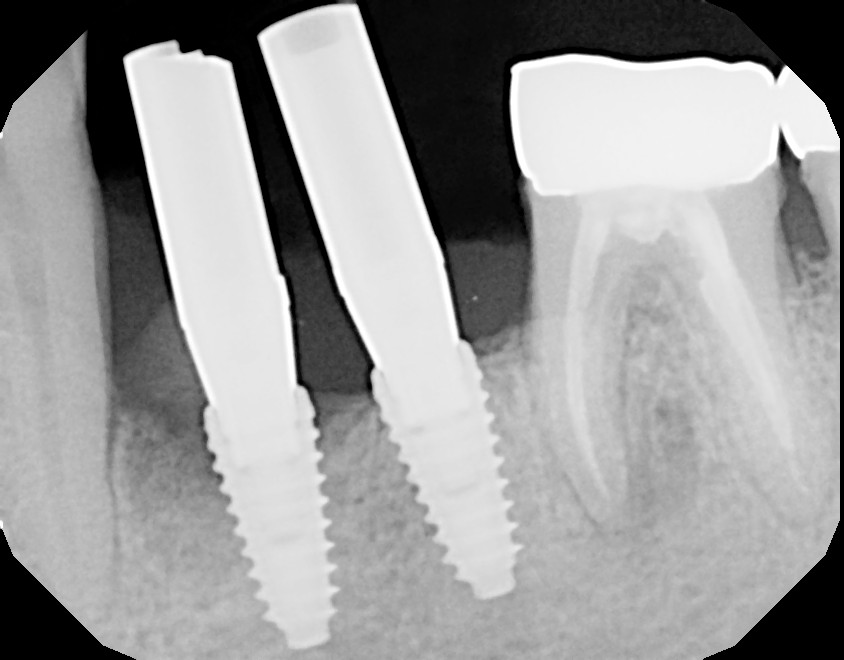

I now understand that the implant is a complex piece of engineering. The bit that is screwed into the jawbone is a hollow, threaded sleeve into which is screwed a secondary part, which you see in the photo above. I turns out to be relatively straightforward to reinstall. What a relief.